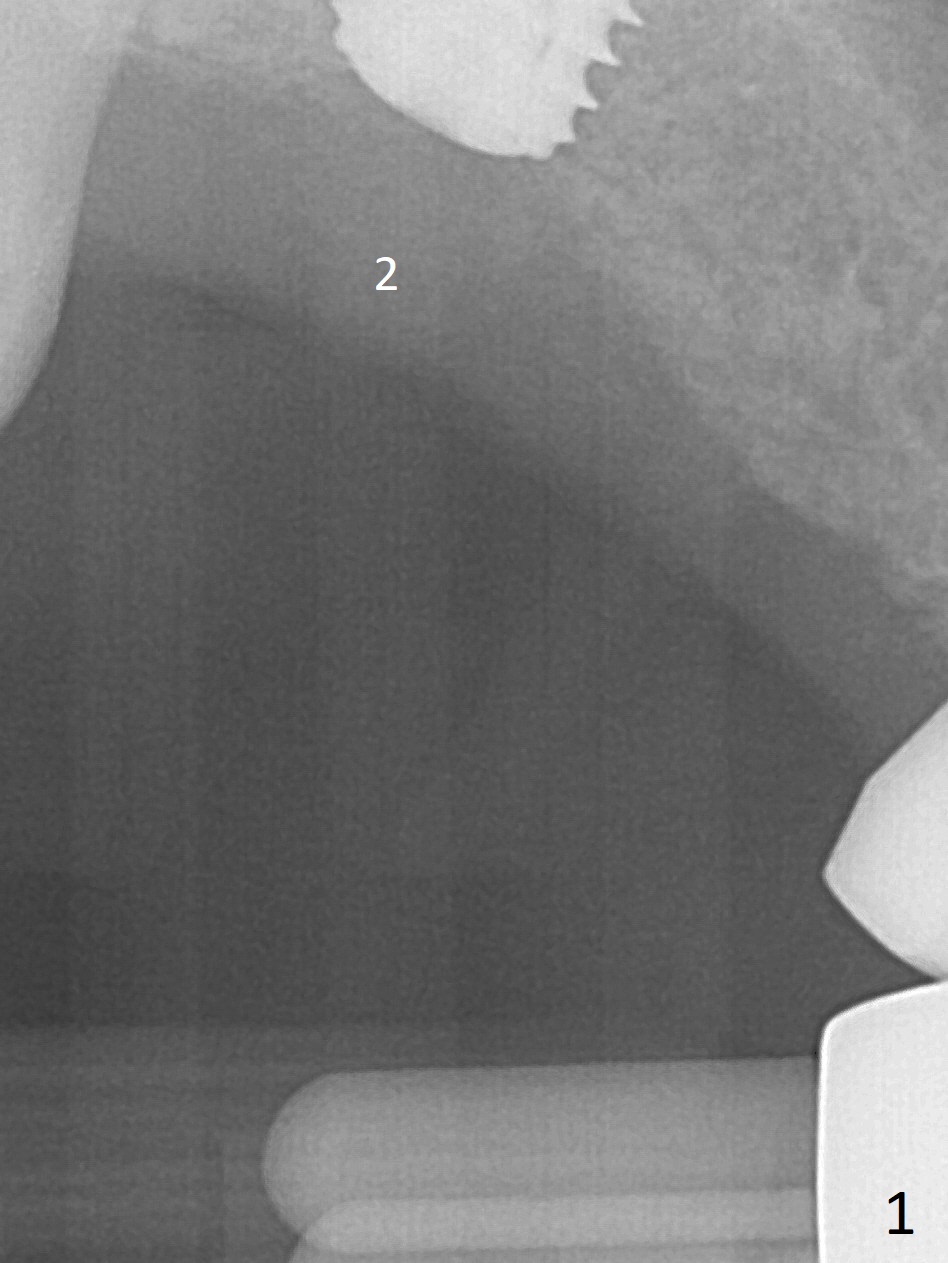

Eight months post socket preservation, the bone density at #2 feels low during osteotomy.  The site is underprep not only in depth, but also in diameter (4.0x7.3 mm with 10.5 mm offset), but a 5x7.3 mm implant is ~ 1 mm shy of the purposed depth.  Following 4.5x7.3 and 4.0x8.5 mm drills (without air leak), the implant reaches the depth, but with ~ 5 Ncm insertion torque (Fig.1).  Placement of the same sized implant at #4 (healed site) is smooth with satisfactory stability (~30 Ncm, Fig.2,3).  Ideally the site of #2 should have been prepared with sinus lift so that the apex of a longer implant would be engaged to the sinus floor for stability.  These two implants heal normally clinically and radiographically 1.5 months postop (Fig.4-6).  Bone surrounds the implant at #2 when it is uncovered 4 months postop (Fig.7).  The retainer at #4 looks short with large gingival embrasure (Fig.8 *) 6.5 months postop.  Finally the patient is ok with it because she does not like gingivectomy.  Provisional should have fabricated (Fig.9 light yellow curved lines) to create gingival scallops with secondary formation of papillae (arrows).